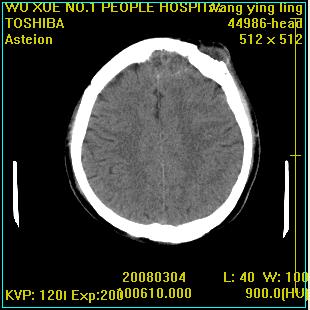

标题: CT12023:女,50岁,头部包块二月,伴轻微头痛,不伴发热。 [打印本页]

标题: CT12023:女,50岁,头部包块二月,伴轻微头痛,不伴发热。

这种病例还是比较多见,起源于颅骨板障,向颅内和颅外生长,考虑血管瘤或嗜酸性肉芽肿,要是有增强ct就好了。

多发溶骨性破坏,骨嗜酸性肉芽肿可能,转移瘤待排除,建议进一步检查。

颅骨多处破坏伴软组织肿块,考虑为转移瘤可能性大。

病灶呈溶骨性骨破坏,考虑嗜酸性肉芽肿可能转移瘤不除外建议追查病史并进一步检查